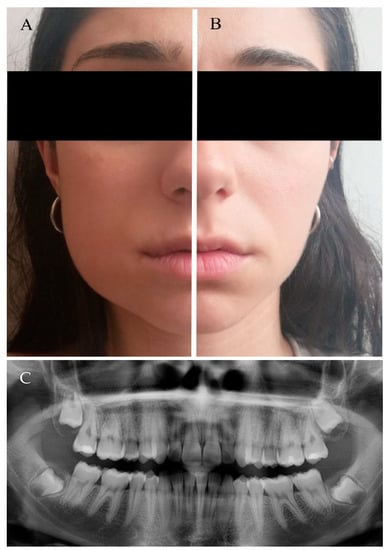

3.1. Patient and Baseline Characteristics

3.2. Clinical Follow-Up and Outcome Measures